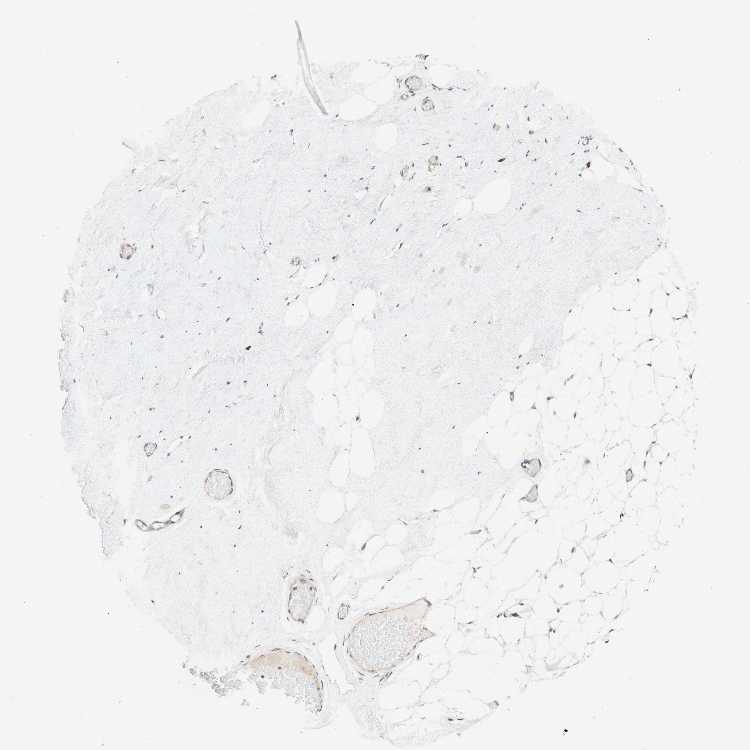

BREAST - Antibody stainingi

Antibody staining in the annotated cell types in the current human tissue is reported as not detected, low, medium, or high, based on conventional immunohistochemistry profiling in selected tissues. This score is based on the combination of the staining intensity and fraction of stained cells.

Each image is clickable and will lead to virtual microscopy that enables deeper exploration of all samples and also displays staining intensity scores, fraction scores and subcellular localization as well as patient and tissue information for each sample.

Antibody CAB010499

Adipocytes Low

Glandular cells Low

Myoepithelial cells Low